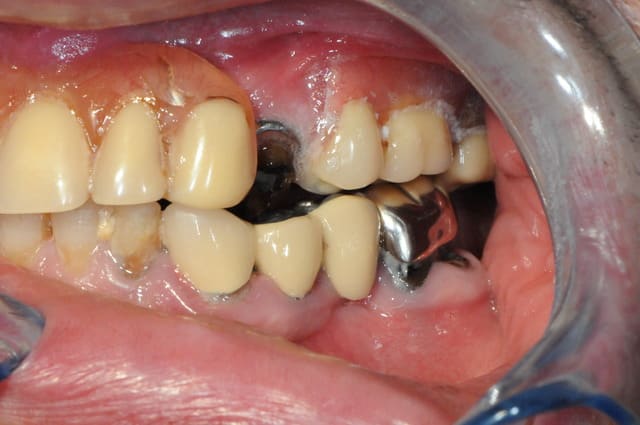

bien sure il faut tout revoir, l'occlusion, la DV, la courbe occlusale, la ligne du sourire...

extraction: 14-15-23-44 et 36 (ou amputation, mais à quoi bon ?)

reprendre la courbe occlusal avec des céram sur 43-46-33-34

bridge sur implant sur 44 -46 et 35-36 (ou 35-37?)

Au maxillaire, quels sont les avantages des implants lorsque l'on fait une prothèse amovible complète ? Essentiellement la possibilité de ne pas avoir de palais en résine.

Je pense que l'on pourrait concentrer son attention sur la mandibule, pour laquelle les solutions amovibles sont souvent moins confortables.

Moi de prime abord j'aurais dit complet haut (pour toutes les raisons qu'a évoquées Marc), et prothèse fixe sur 44 et implants 35 36(37?) 45 46.

Au plus simple au mieux. Et niveau budget ça doit pas être inaccessible.

C'est sûr que c'est le patient qui décide, mais je me souviens d'un patient à qui on avait mis au maxillaire 4 implants + barre pour éviter le palais, et qui quelques années plus tard m'a avoué qu'il avait été déçu du résultat.

Il pensait que ça révolutionnerait sa vie, et en fait son complet sur barre tient bien, mais l'ancien aussi tenait bien.. Quant au palais évidé (évité?), il m'a dit s'être rendu compte qu'en définitive ça ne changeait pas grand-chose dans sa vie quotidienne...

Donc pour moi, ici, si le patient ne se plaint pas de la tenue de son partiel, c'est complet haut en 1ère intention.

implants si gros problème de tenue, ou demande expresse.